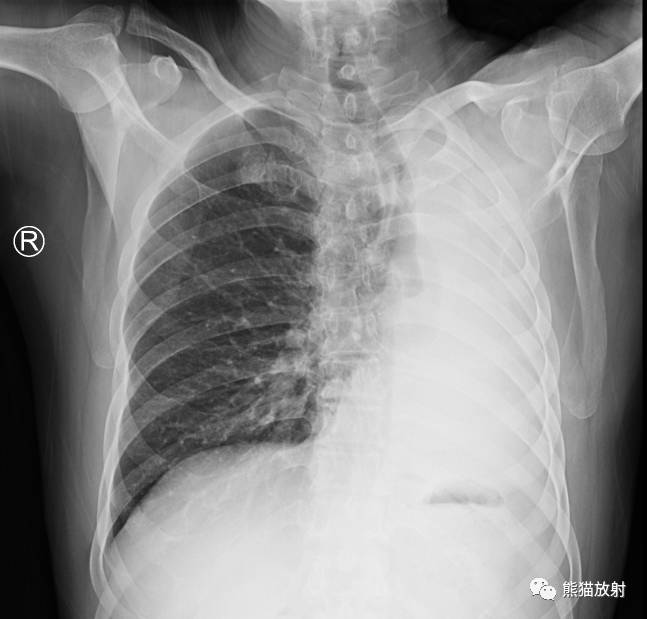

↓ 左肺全肺不张(患者肺野密度增高,胸廓塌陷,气管、纵隔左移) 原因?进一步行CT增强、支气管镜检查。